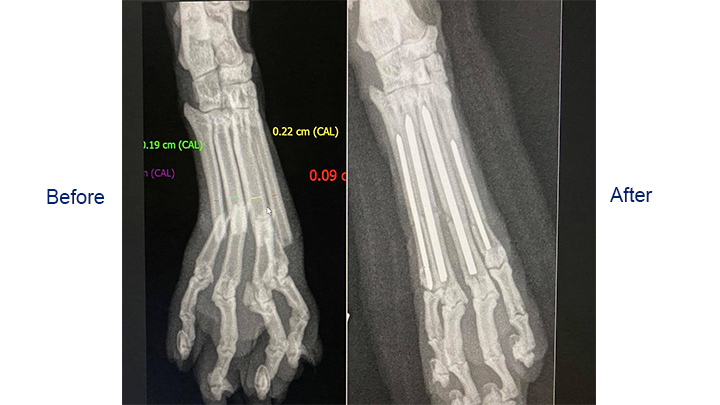

As correctly suspected by Medivet Shawbirch’s vet, Phillipa had broken multiple bones in her paw, making it unstable.

In many cases, a pet may only break one of their bones in the paw, and in that situation, the other bones can often be allowed to act as an internal splint, meaning surgery wouldn’t be necessary. However, in Phillipa’s case, multiple bones were broken making the whole foot unstable, so surgery was the best option.

A support dressing was applied overnight to keep the swelling to a minimum and to keep her comfortable, ready for surgery the next day. During the surgery, Duncan was able to stabilise the broken bones with internal pins to allow the bones of the paw to heal in their normal positions.